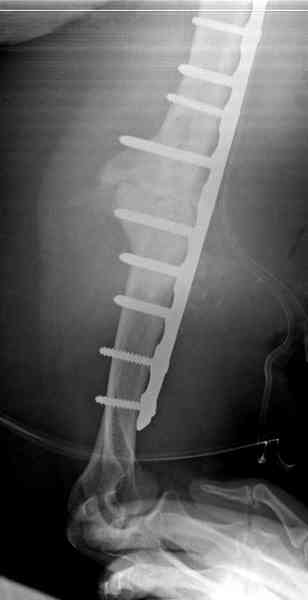

Первичную пластину убрали недели 6 назад из переднего оригинального доступа, и из-за подозрительности тканей вокруг пластины, решили провести реконструкцию поэтапно.

После промывки и дебридмента для уверенности уложили антибиотический цемент. Культура из раны в последующем была отрицательная.

Хотя сам не стороннник применения более массивных

имплантов для плеча, но для этого случая сделали

исключение. На снимке 4А диаметр мягких ткани около 20 см, при весе больной более 135 кг, и также выступление Андрея Волны подстегнуло к применению более массивной 4.5 мм локинг пластины.